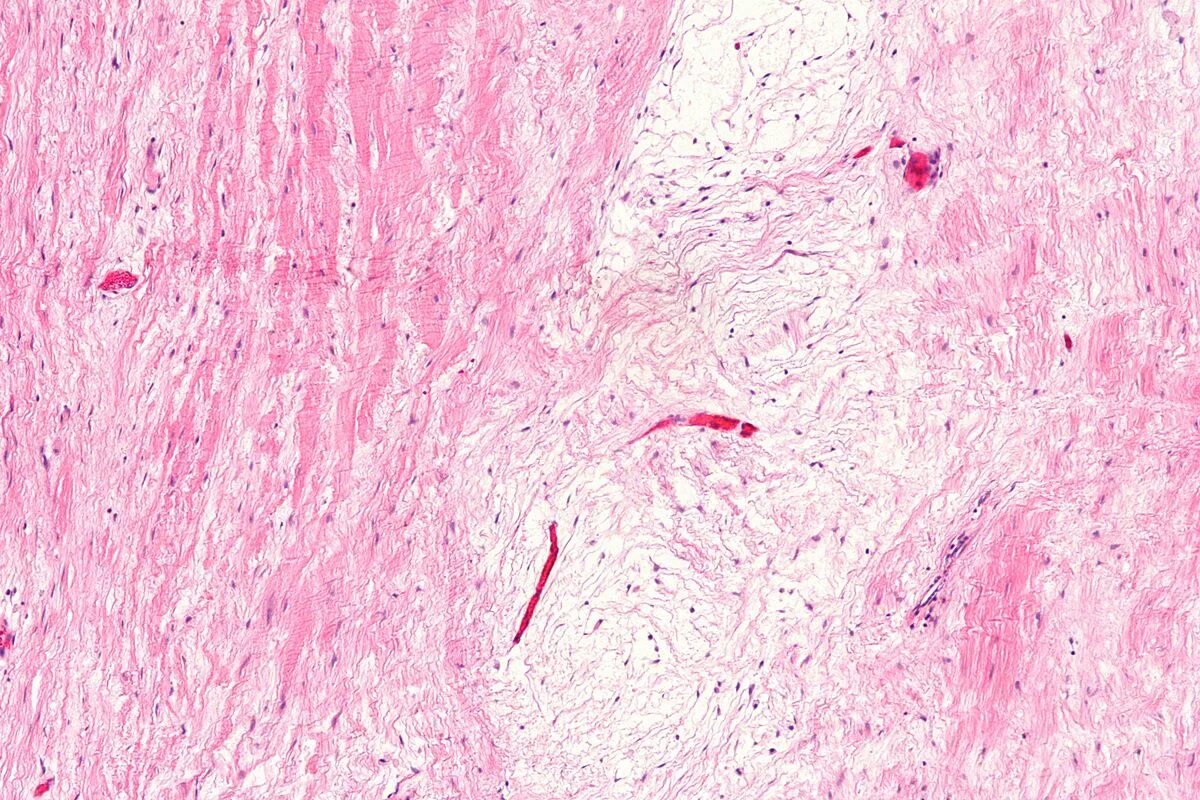

Гистология челюстей